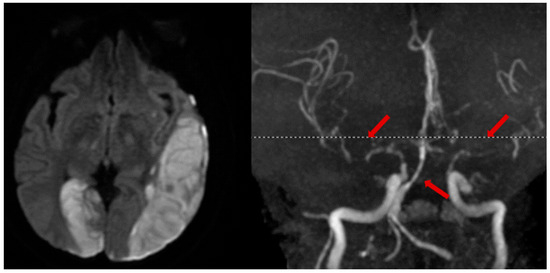

2.4. Post-Traumatic Vasospasm

- Martin, N.A.; Doberstein, C.; Zane, C.; Caron, M.J.; Thomas, K.; Becker, D.P. Posttraumatic cerebral arterial spasm: Transcranial Doppler ultrasound, cerebral blood flow, and angiographic findings. J. Neurosurg. 1992, 77, 575–583. [Google Scholar] [CrossRef] [PubMed]

- Zubkov, A.Y.; Lewis, A.I.; Raila, F.A.; Zhang, J.; Parent, A.D. Risk factors for the development of post-traumatic cerebral vasospasm. Surg. Neurol. 2000, 53, 126–130. [Google Scholar] [CrossRef] [PubMed]

- Kramer, D.R.; Winer, J.L.; Pease, B.A.; Amar, A.P.; Mack, W.J. Cerebral vasospasm in traumatic brain injury. Neurol. Res. Int. 2013, 2013, 415813. [Google Scholar] [CrossRef]

- Weidauer, S.; Lanfermann, H.; Raabe, A.; Zanella, F.; Seifert, V.; Beck, J. Impairment of cerebral perfusion and infarct patterns attributable to vasospasm after aneurysmal subarachnoid hemorrhage: A prospective MRI and DSA study. Stroke 2007, 38, 1831–1836. [Google Scholar] [CrossRef] [PubMed]